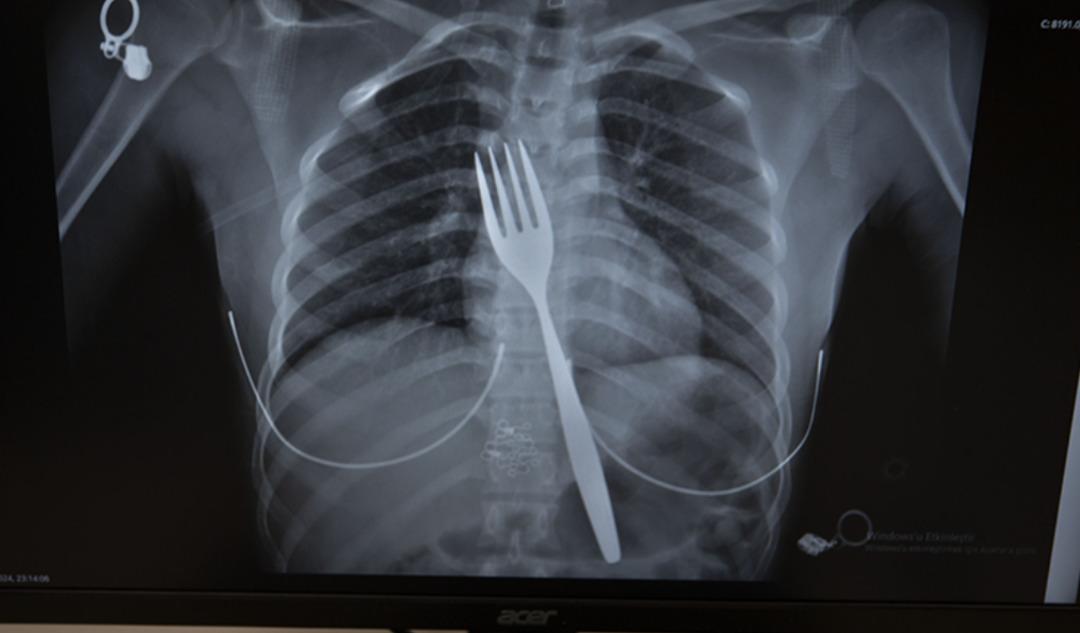

Söke'de ikamet eden yabancı uyruklu EE (18), çatal yutma şikayetiyle ambulansla Aydın Adnan Menderes Üniversitesi Hastanesi'ne (ADÜ) götürüldü. Burada röntgeni çekilen hastanın yemek borusunda 18 santimetrelik çatal olduğu belirlendi.

Uzmanlar endoskopi yaparak çatalı ağızdan çıkarmaya çalıştı. Ancak yemeğe ve nefes borusuna zarar verme ihtimali nedeniyle midenin kesilip çatalın çıkarılmasına karar verildi.

ADÜ Tıp Fakültesi Göğüs Cerrahisi Anabilim Dalı Öğretim Üyesi Dr. Salih Çokpınar ve Genel Cerrahi Anabilim Dalı Dr. Öğretim Üyesi Akay Edizsoy'un koordine ettiği operasyonda midede kesi yapılarak çatal çıkarıldı.

Edizsoy, vakayı ilk duyduğunda şaşırdığını belirterek, şöyle konuştu: “Büyük bir çatalın tamamen yutulması sonucu oluşan bu vakayı ilk duyduğumda doğru olmadığını düşünmüştüm. Hasta 18 yaşında ve 18 yaşındaydı. Yabancı uyruklu. Türkçesi biraz zayıf olduğu için bir yanlış anlaşılma olabileceğini düşündük ama hastayı çektiğimizde aslında çatal yutuyordu.” “Yemek borusunda olduğunu gördük.” dedi.

“Bu yüzden çok endişelendik. Ancak endoskopide ciddi bir lezyonun olmadığını gördük. Oldukça büyük olduğundan ve endoskopik aletlere uygun olmadığından endoskopi ile çıkarılamadı. Büyük bir masa çatalı olduğu için kendine ait. ağırlıktır. Bir çivi gibidir, bir iğne gibidir. “Tutulamaz ve çıkarılamaz. Bu nedenle karından kesi yaparak mideye ulaşıp midenin içinden çıkarma stratejisi izledik. Bu ameliyatla bu çatalı oradan çıkarmayı başardık.”